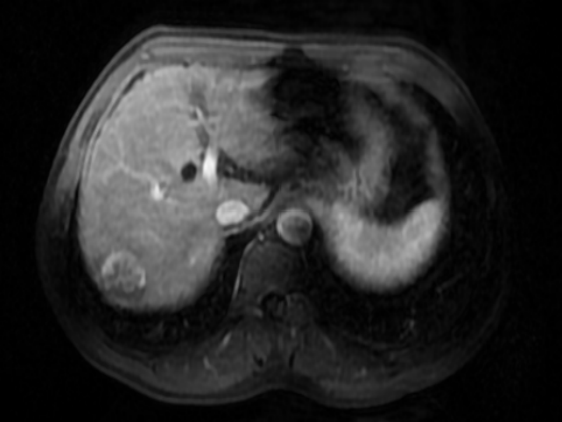

腹部MRI(2019-10-09):肝内信号不均匀,多发弥漫性T2WI稍低信号,肝S7段可见类圆形异常信号,T1WI呈稍低信号,T2WI-FS呈稍高信号,DWI呈明显高信号,增强扫描后动脉期病灶明显强化,门脉期及延迟期病灶强化程度明显下降,呈快进快出改变,病灶大小31 × 31 × 32 mm,可见假包膜形成,余肝实质内未见强化病灶,肝血管走行正常,腹膜后未见肿大淋巴结,腹腔内未见积液征象。